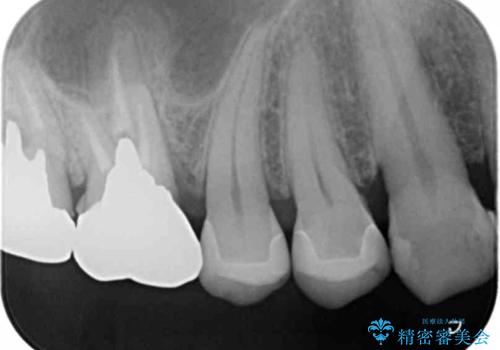

- 笑った時にチラつく銀歯が気になるから白くしたいとのことで来院。

銀の詰め物を除去し、残った歯の量が多かったためセラミックインレーでの修復となりました。

- 右上56 セラミックインレー 77000円×2本費用は治療当時の料金となります